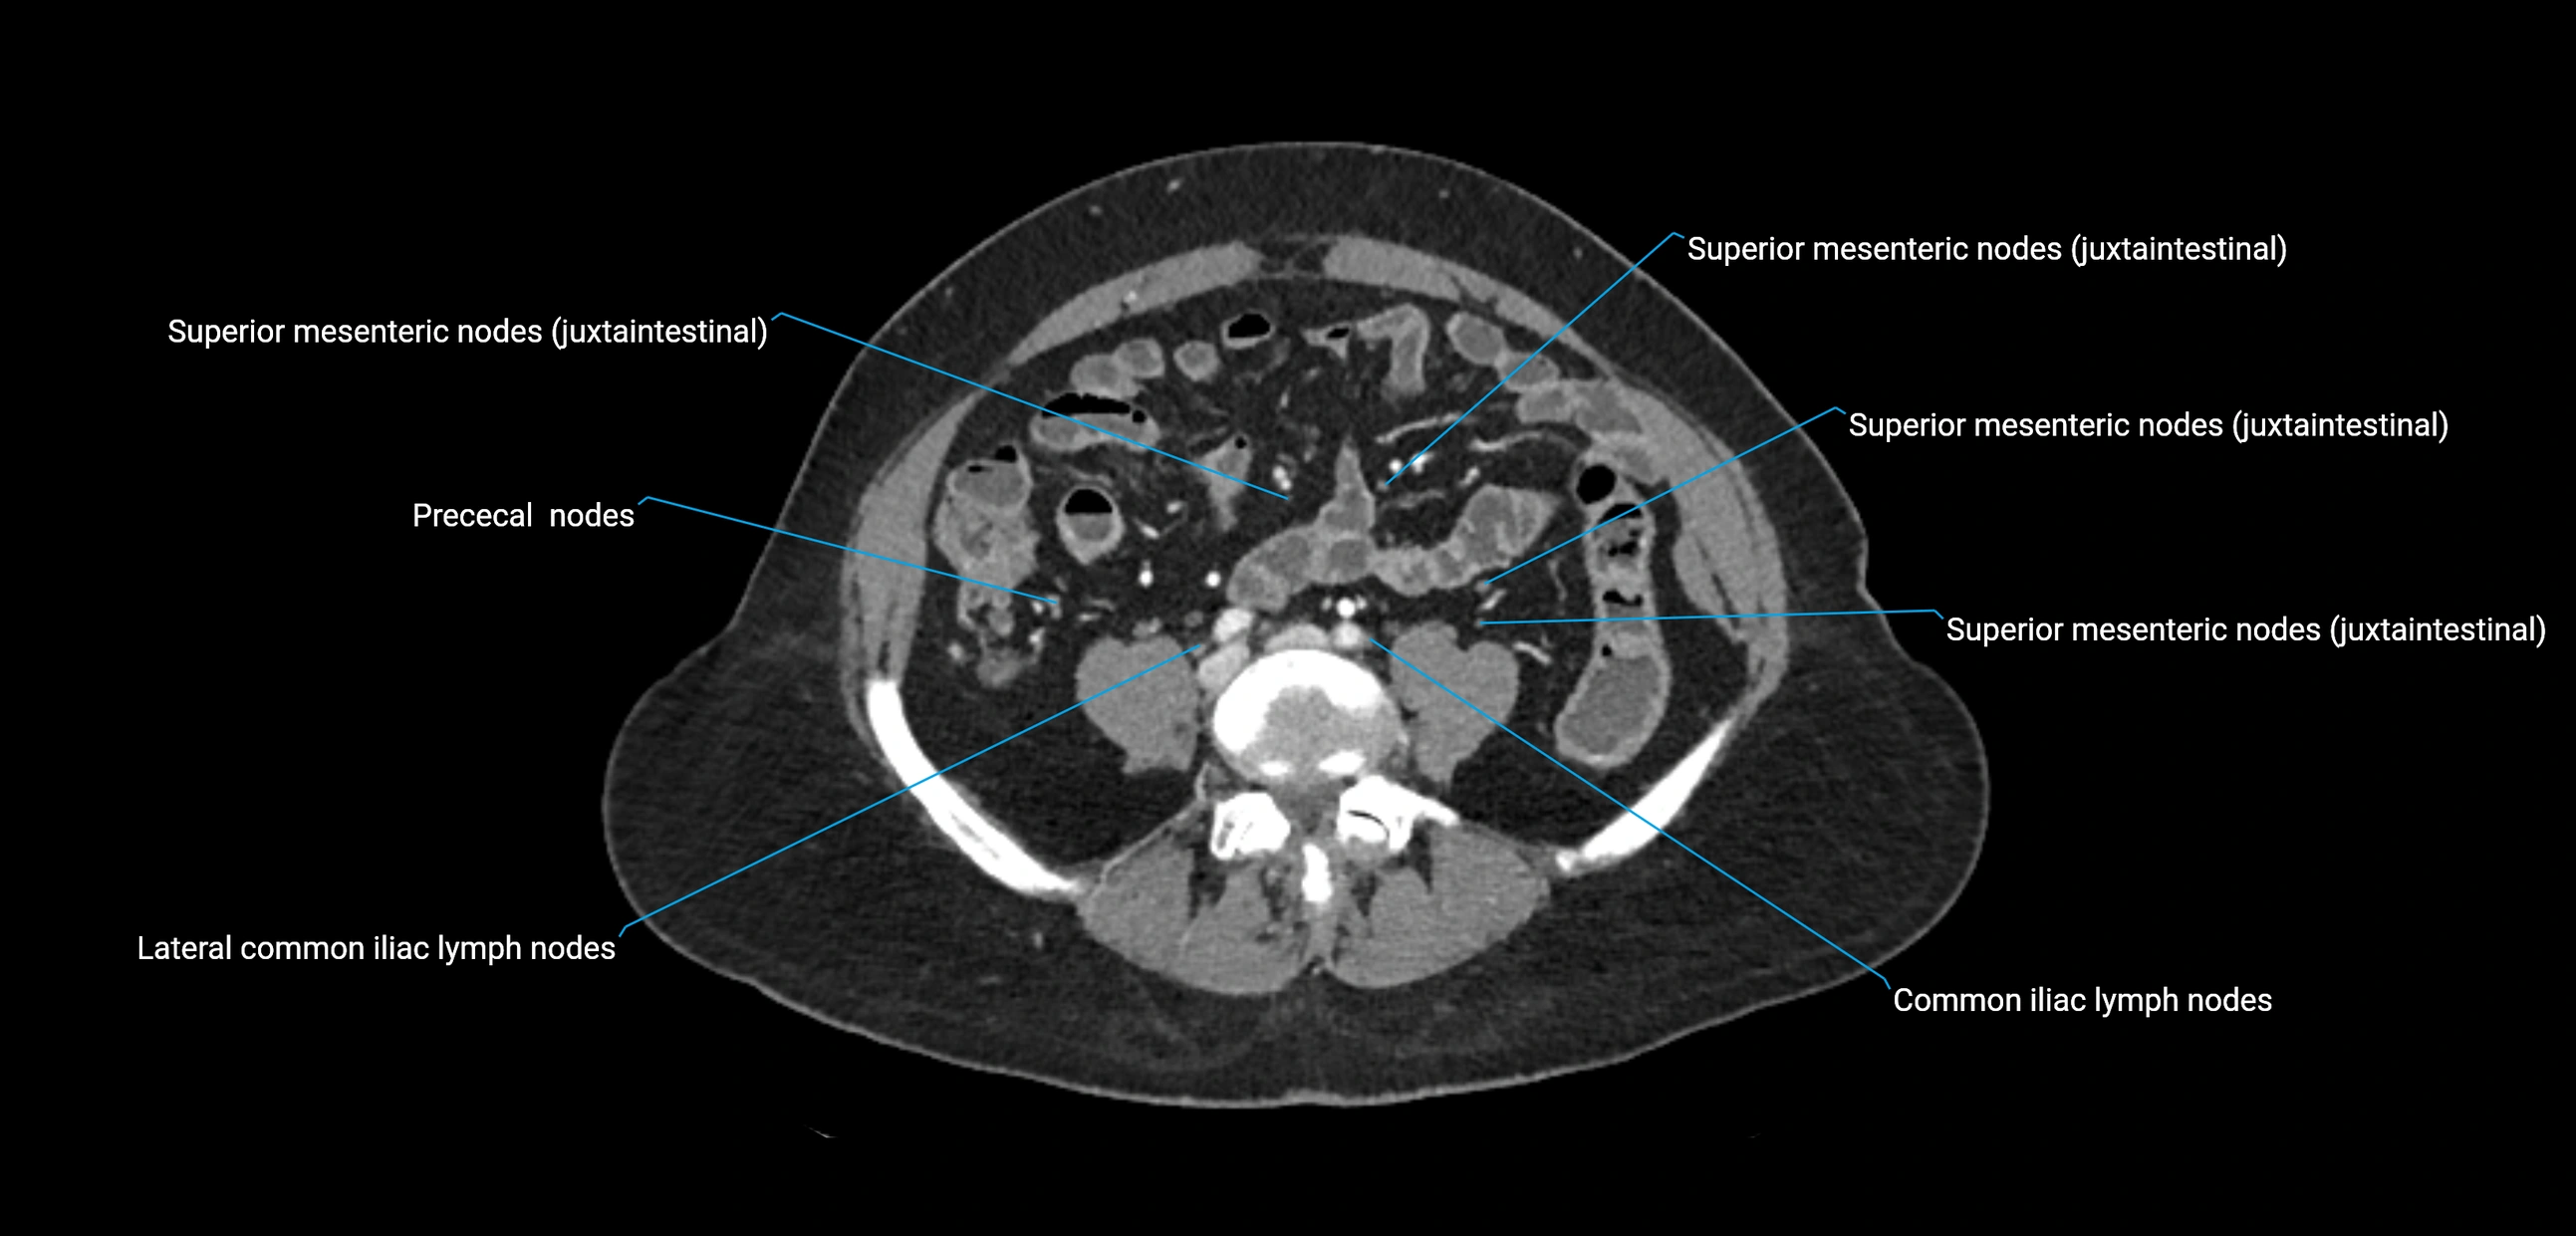

CT Appearance

CT Pre-Contrast:

• Nodes appear as soft-tissue density nodules adjacent to the aorta and IVC

• Calcification may be seen in chronic infections (e.g., tuberculosis)

CT Post-Contrast:

• Normal nodes enhance homogeneously

• Malignant nodes may show heterogeneous enhancement, central necrosis, or conglomerate formation

• Size >1 cm short axis is suspicious, though morphology and distribution are equally important

CT Venography (CTV):

• Demonstrates nodal encasement or compression of adjacent vessels (aorta, IVC, renal veins)

• Useful in staging testicular and ovarian malignancies

• Provides 3D reconstructions for retroperitoneal lymph node dissection planning